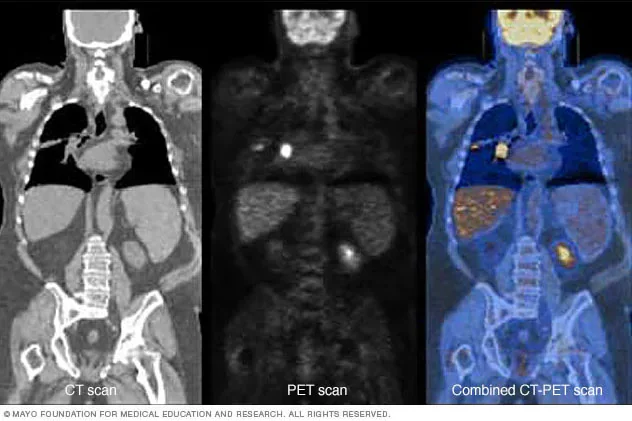

• Se desarrolla la TC de emisión de positrones (PET/CT), que combina la información de la TC y PET para proporcionar imágenes más precisas y detalladas de la estructura y función del cuerpo.

Se desarrolla la TC de emisión de positrones (PET/CT), que combina la información de la TC y PET para proporcionar imágenes más precisas y detalladas de la estructura y función del cuerpo.